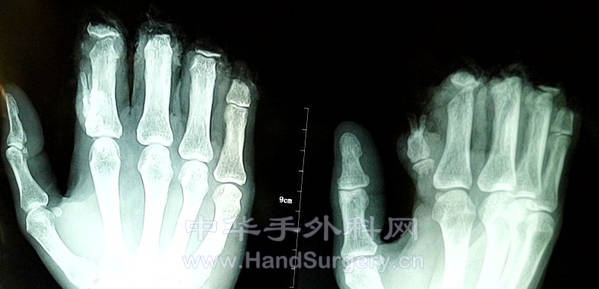

马*,男,44岁。因电锯伤右食中环小指完全离断伤入院。右食指无再植条件予残端修整术,右中环小指予关节融合短缩再植术。

术前X光片

术后X光片